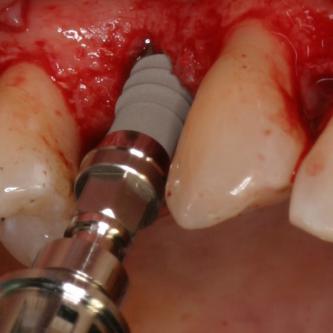

Exemple 7: Un implant au niveau de la deuxième prémolaire inférieure gauche.

Exemple 7: Le moignon vissé sur l'implant.

Exemple 7: La couronne en place

Exemple 7: vue depuis dessus